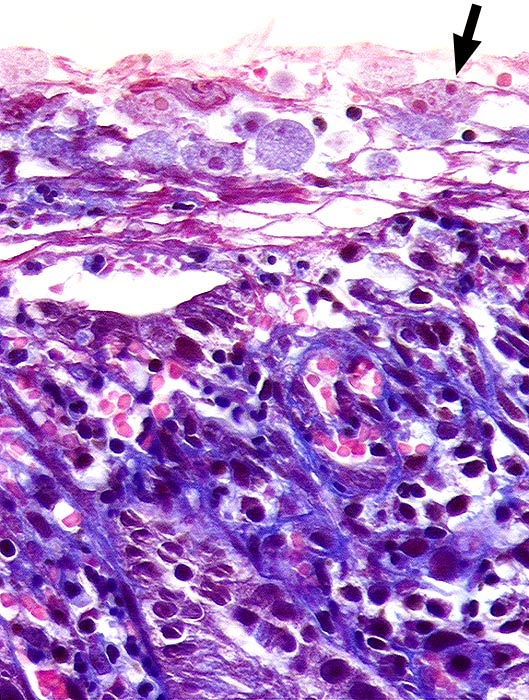

Amöbenkolitis

Entzündung infektiös

Kolon